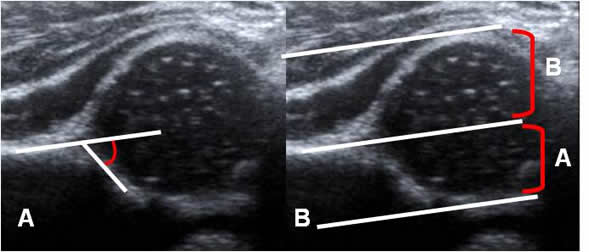

Angulo alfa:

Trazo sobre una vista coronal de ecografía, sobre la parte media del acetábulo. Se mide entre la línea de base (Prolongación del iliaco) y la línea del techo óseo (Del borde inferior del iliaco, hasta el extremo óseo del acetábulo). Representa la excavación ósea del acetábulo y su amplitud normal debe ser igual o mayor de 60º y disminuye en casos de displasia. (19, 20). (Fig 62).

Un ángulo mayor de 60º es normal para cualquier edad. Entre 50º y 59º, puede ser normal para niños menores de 3 meses, pero se recomienda el seguimiento y un ángulo menor de 50º, es anormal en cualquier edad. (19). (Fig 64).

Otra relación que se puede medir es la cobertura acetabular. Además de la línea de base, se trazan otras 2 líneas paralelas al borde superior e inferior de la cabeza femoral. (19). Se mide la relación entre la distancia inferior y superior y se obtiene el porcentaje del cubrimiento, que debe ser mayor del 50% y disminuye en la displasia. (19). (Fig 63 y 64).

Fig 62. Angulos de la cadera.

Ecografía. Línea de base (Flecha delgada), línea del techo óseo (Flecha gruesa) y línea del techo cartilaginoso (Punta de flecha). Angulo alfa normal, con amplitud mayor de 60.

Fig 63. Cubrimiento de la cadera.

Ecografía. Línea de base, línea superior (Flecha delgada) y línea inferior (Flecha gruesa). La relación entre A/ B, debe ser mayor del 50%.

Fig 64. Displasia de cadera.

Ecografía. A: Disminución del ángulo alfa (50) y B: Disminución de la relación A/B, por displasia.